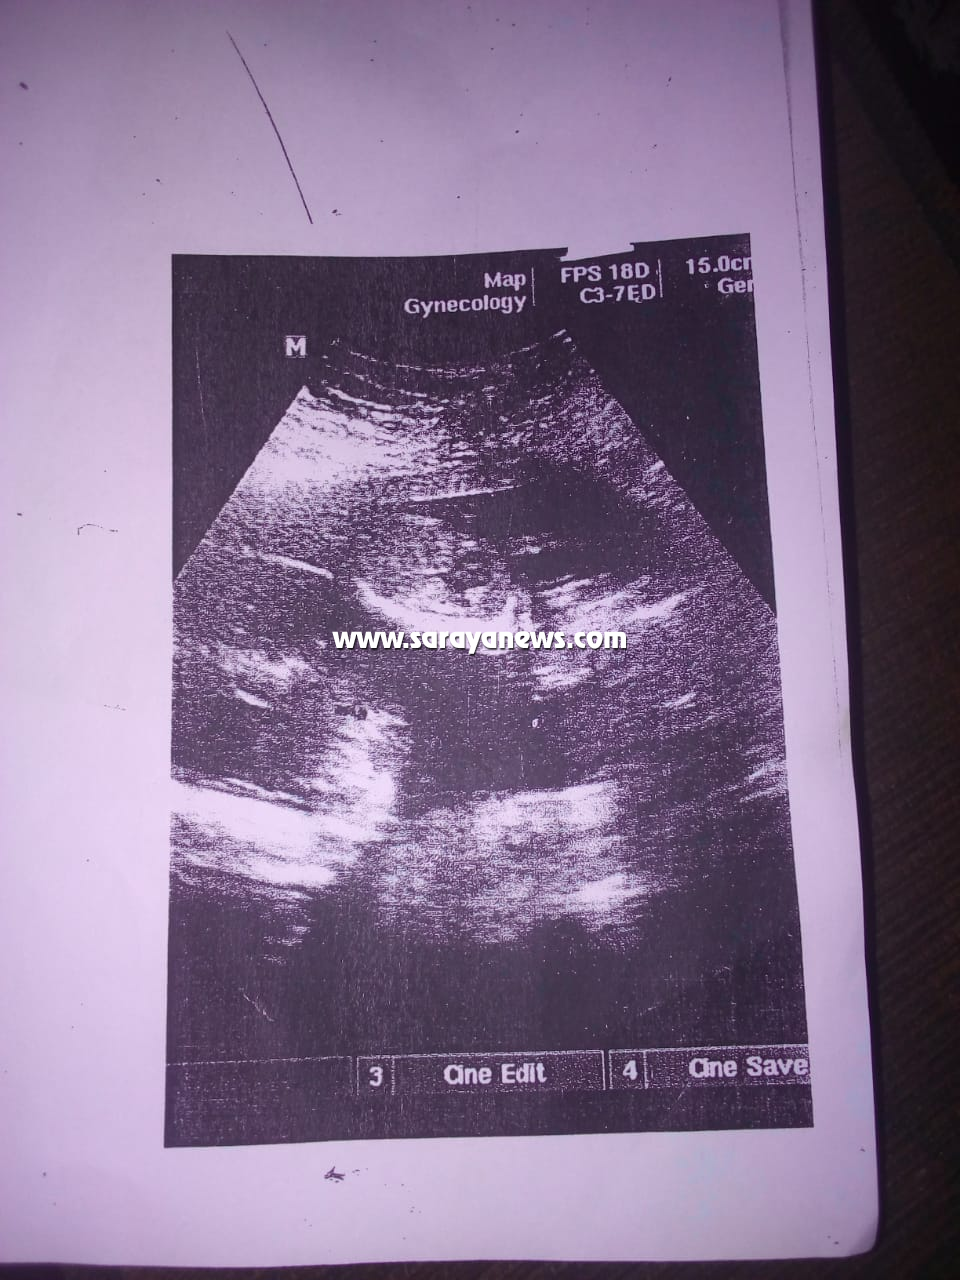

وبحسب رواية الأم نجلاء لسرايا قالت: "أنا كنت حامل بتوأم ومعي تقارير من بداية الحمل إلى آخر شهر من الحمل وحتى لحظات الولادة تفيد بأنني حامل بتوأم، وتضيف؛ كنت أراجع عند أكثر من طبيب نسائية ومعي صور شعاعيه للأجنة، وملف كامل من الطبيب المتابع لحالتي أثناء فتره الحمل وهو الطبيب ربحي خلف أخصائي النسائية والتوليد في المركز الطبي الفرنسي بمخيم غزة، حيث أخبرني في آخر مراجعة قمت بها لديه أن وضع التوأم جيد وكانت هذه المراجعة في آخر شهري الثامن، وبين لي حينها أن أوزان التوأم تصل لأكتر من(2700) غرام لكل طفل منهم، وأوضح لي في نفس الجلسة أن احد الأجنة نازل في الحوض -بمعنى اقتراب موعد الولادة– وأخبرني أنه يجب علي أن اذهب بعد عشر أيام من عيد الفطر لإحدى المستشفيات المتخصصة بالولادة، لتحديد موعد الولادة القيصرية، كون ولاداتي الستة السابقة كلها تمت بعمليات قيصرية للصعوبة الفائقة بولادتي الطبيعية".

تابعت نجلاء.. "توجهت بعدها إلى الطبيب منذر في عيادته الخاصة ببيته وهو طبيب نسائية وتوليد بمستشفى جرش الحكومي بتاريخ: (23 ـ 06 ـ 2018م) وتم فحصي من قبله حينها، وأكد لي أن التوأم بصحة جيده وبين أن طفل منهم رأسه نازل في الحوض، وأضاف لي انه احتمال أن ألد في وقت قريب، ونصحني بالتوجه إلى مستشفى جرش الحكومي، لحجز موعد لعملية الولادة القيصرية كون ولاداتي السابقات صعبة ولا تتم إلا بالعملية القيصرية، واتصلت على المستشفى في يوم ثلاثاء وأعطوني موعدا لعيادة الدكتور هاني بتاريخ: (3 ـ 07 ـ 2018م)".

تابعت نجلاء.. "ذهبت في نفس اليوم بعد زيارة الطبيب منذر إلى عيادة الدكتور عوف عفانة أخصائي النسائية والتوليد بعيادته الخاصة بمخيم غزة، حيث كنت أراجع عنده كل عشر أيام لأطمئن على أطفالي، وهذا الدكتور كان يتابع حالتي منذ الشهر الرابع إلى آخر يوم قبل ذهابي إلى الولادة ففحصني وطلب مني أن أُسرع بإجراء العملية مؤكدا لي أن أوزان الأجنة بازدياد مستمر".

وتابعت نجلاء.. "ذهبت في (3 ـ 07 ـ 2018م) إلى عيادة الدكتور هاني العقيلي وفحصني سريريا من خلال جهاز (الالترا ساوند) وقال لي: إن التوأم وضعه جيد ودقات القلب لديهما جيدة، وأضاف قائلا لي: إنا ما بقدر أعملك العملية أنتي حامل بتوأم وعندك ولادات قيصريه سابقة وأنا احتاج أكثر من دكتور وتخصص لمساعدتي في العملية هذه، وأعطاني تحويله طارئة إلى البشير، وقلت له بصير أروح اعملها في بديعة لأني أنجبت فيها مرات عديدة، فقال لي: ما في مشكلة روحي على بديعة".

تابعت نجلاء.. "عدت لبيتي من مستشفى جرش، وذهبت مساءً إلى الدكتور عوف وشرحت له عن التحويلة ووضع التوأم، فبادر بفحصي على جهاز (الالترا ساوند) وأكد أن أطفالي بخير وصحتهم جيده ونبضهم جيد وان أوزانهم اكتر من (2700 غم) لكل طفل وكرر طلبه مني الاستعجال بالعلية".

تابعت نجلاء.. "توجهت في (05 ـ 07 ـ 2018م) إلى مستشفى بديعة برفقة والدتي وزوجي ووصلنا المستشفى الساعة الثانية عشر ونصف ليلا، وأخبرتهم إنني حامل بتوأم، وتم فحصي من قبل الدكتور المقيم مثنى الشوحة في المستشفى حينها، وأكد لي أن توأمي أحياء ونبضهم موجود وجيد، وبين لي أن احدهم رأسه نازل في الحوض، وسألني مستغربا: هل زارعتيهم زراعه، وأجبته فورا: لا.. وأردفت تقول له: في عائلتي ننجب توائم مرات عديدة. وأضافت نجلاء.. في الأثناء قامت الدكتورة المقيمة رزان فؤاد حداد بإحضار أوراق وضعت بصمتي عليها".

تابعت نجلاء.. "حينها ذهب الطبيب المقيم واحضر لي دكتورة أجنبية اسمها   وفحصتني مرة أخرى، وسألتني: بتراجعي في أي مكان.. أجبتها لا ارجع، فقالت: ما معك أي ورقه من أي مركز صحي، فقلت لها: لا.. ما معي– حيث كنت خائفة ما يقبلوا يعملوا لي عملية لأني من جرش فأخفيت موضوع التحويلة وأوراق المراجعة لأنهم في المستشفى لا يستقبلون من خارج محافظة اربد- وتم عمل فحص لدقات القلب وتأكدوا أن التوأم بصحة جيدة".